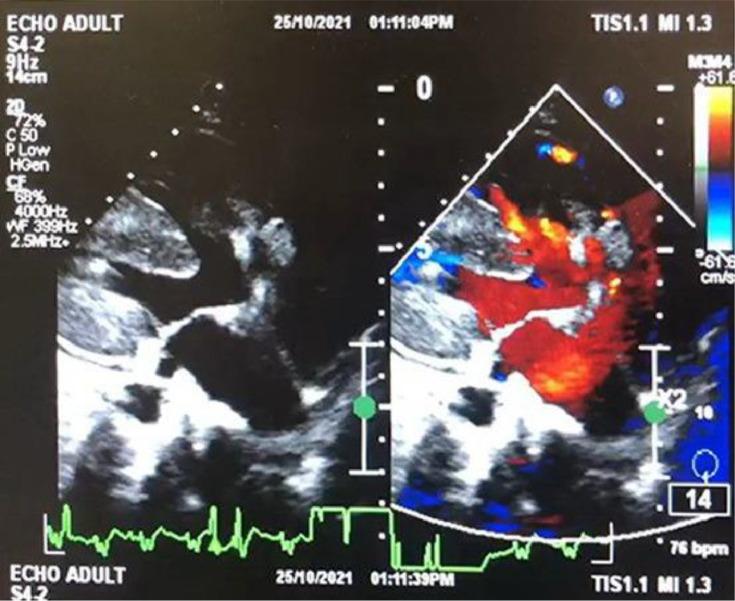

Double outlet right ventricle (DORV) is a congenital cardiac malformation that occurs in 1%-3% of individuals with congenital heart defects. Cardiac magnetic resonance imaging (MRI) may play an important role in the anatomy of the ventricular septal defect, functional status of both ventricles, and in identifying any residual stenosis or regurgitation or coexistent anomalies. Here, we present a case of a 28-years-old woman who came to our emergency department with shortness of breath. The patient felt shortness of breath on exertion and improved with rest. Clinical examination showed no abnormalities except low oxygen saturation of 65%. After echocardiography and cardiac MRI were done, it was concluded that she had a double outlet right ventricle with peri membranous ventricular septal defect (VSD), pulmonary hypertension, and pericardial effusion. This study highlights the role of cardiac MRI in assessing DORV.

右心室双出口(DORV)是一种先天性心脏畸形,在先天性心脏缺陷患者中发生率为1%-3%。心脏磁共振成像(MRI)在室间隔缺损的解剖结构、双心室功能状态以及识别任何残余狭窄或反流或并存异常方面可能发挥重要作用。在此,我们报告一例28岁女性患者,她因呼吸急促前来我院急诊科就诊。患者在运动时感到呼吸急促,休息后症状改善。临床检查除氧饱和度低至65%外无异常。经超声心动图和心脏MRI检查后,得出结论她患有右心室双出口合并膜周部室间隔缺损(VSD)、肺动脉高压和心包积液。本研究强调了心脏MRI在评估DORV中的作用。